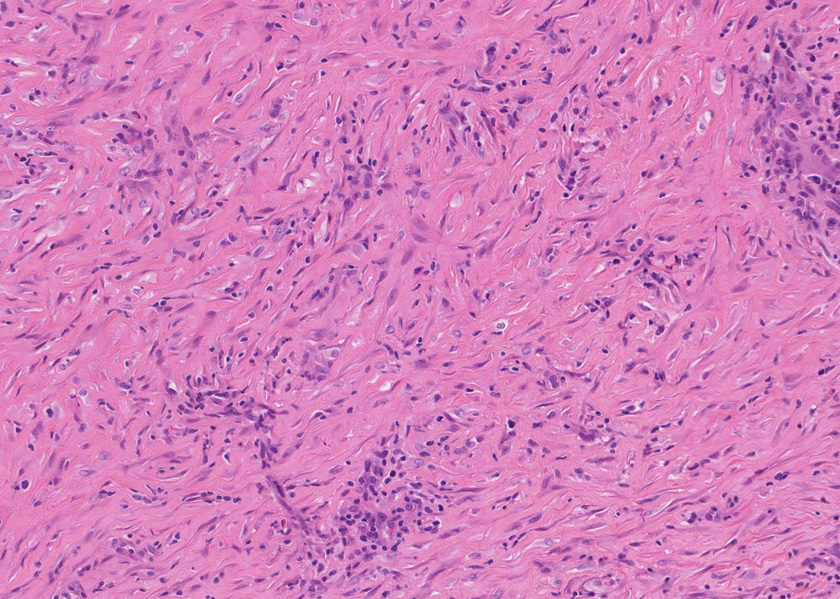

線維化組織に類円, 葉巻型淡明な核の紡錘型細胞が増生している。免染SMA陽性。血管周囲に慢性炎症あり。

組織像は膵腫瘤B, Cと同じくinflammatory myofibroblastic tumorである。島状に形質細胞主体の慢性炎症が強い。腹膜腫瘤には腺管は認められない。